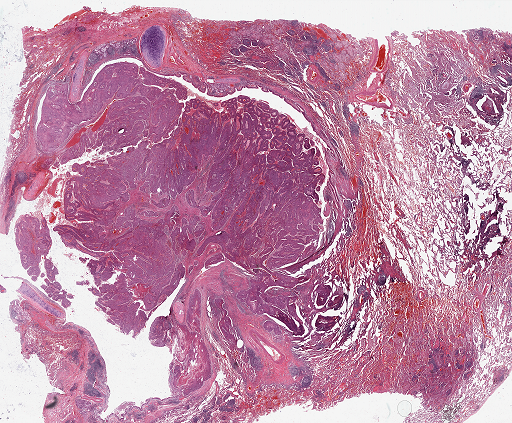

For qualitative ROI detection evaluation check Fig. 3.

Refer to caption

(a)

(b)

Figure 3: Qualitative view of ROIs recognized by Suffy through its Patch Classification. (a) An example WSI from the test set of the CAMELYON16 dataset [3]. (b) ROIs are identified by Snuffy with black lines delineating the ground truth ROIs.